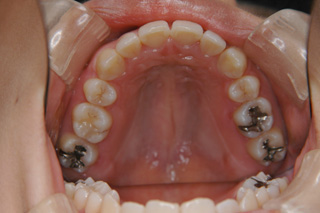

「顎顔面変形症及び不正咬合の外科的矯正治療、外科的矯正治療後の顎間固定」用の骨接合用品(オーソアンカー SMAPシステム)

(上下顎前突/上下顎小臼歯抜歯)

装置撤去です。動的処置は2年弱でしたので、歯の移動させた距離で考慮すると、比較的短い治療期間でした。極めてよい咬合状態が得られたと思います。いずれも強い固定源を利用した結果の成果と考えられます。まだ、オーソアンカー SMAPシステム がそのまま残っているのが見えますが、もう必要ないので撤去して貰う予定です。今後は保定治療に移行し、数年にわたって咬合の安定状態を管理していきます。